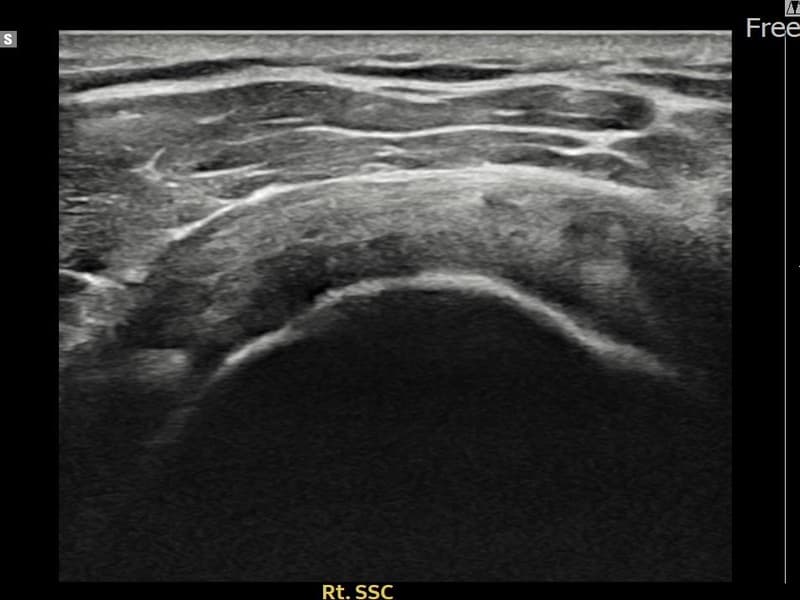

시술 전 초음파 측정 결과 파열 크기는 7mm × 3mm (힘줄 두께의 약 28% 결손)로 확인되었습니다. 시술 전 초음파에서 우측 견갑하근건 관절면측의 에코 단절과 힘줄 결손 소견이 확인되었습니다. 시술 후 초음파에서 파열 부위에 재생 조직이 형성되고 힘줄 연속성이 회복된 것이 관찰되었습니다.

30대 후반 남성 환자분으로, 우측 어깨 앞쪽 통증과 함께 팔을 안쪽으로 돌리거나 등 뒤로 보내는 동작이 어려워 내원하셨습니다. 헬스 훈련 중 부상 이후 증상이 시작되었으며, 견갑하근건 손상은 극상근건 손상에 비해 발견이 늦은 경우가 많아 주의가 필요한 부위입니다. 초음파 검사에서 우측 견갑하근건 관절면측 부분파열이 확인되었으며, 초음파 유도 하 축소봉합술을 시행하였습니다. 시술 후 내회전 강화 재활 운동을 통해 꾸준히 회복하였고, 시술 후 추적 초음파에서 힘줄 연속성이 회복되어 정상 생활에 복귀하셨습니다.